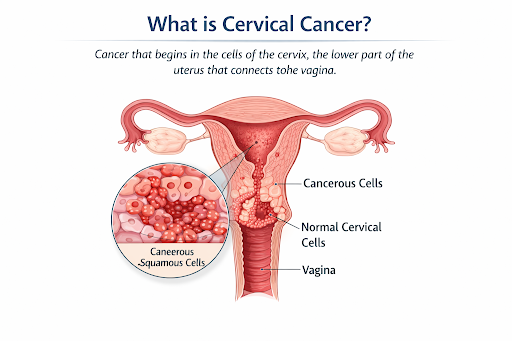

What is Cervical Cancer?

Cervical cancer develops in the cervix, the lower narrow part of the uterus that connects the uterus to the vagina. The cervix plays a key role in menstruation, fertility, and pregnancy. Cervical cancer occurs when cells in this area grow and divide uncontrollably.

Main Types of Cervical Cancer

● Squamous Cell Carcinoma: Starts in the outer cervix (exocervix); most common type.

● Adenocarcinoma: Starts in glandular cells of the inner cervix (endocervix); less common but increasingly seen.

Cervical cancer often develops slowly, and early symptoms may be subtle or absent.

Cervical cancer develops in the cervix, the lower narrow part of the uterus that connects the uterus to the vagina. The cervix plays a key role in menstruation, fertility, and pregnancy. Cervical cancer occurs when cells in this area grow and divide uncontrollably.

Main Types of Cervical Cancer

● Squamous Cell Carcinoma: Starts in the outer cervix (exocervix); most common type.

● Adenocarcinoma: Starts in glandular cells of the inner cervix (endocervix); less common but increasingly seen.

Cervical cancer often develops slowly, and early symptoms may be subtle or absent.

2. Where It Begins +

Cervical cancer usually begins in the cells lining the cervix, most commonly in the transformation zone, where the outer and inner cervix meet. This area is more vulnerable to damage, especially from persistent high-risk HPV infection.

Cervical cancer usually develops slowly over many years. Persistent high-risk HPV infection can interfere with normal cell growth regulation, leading to abnormal cell changes. These abnormal cells may form precancerous lesions, which can progress to cancer if not detected and treated.